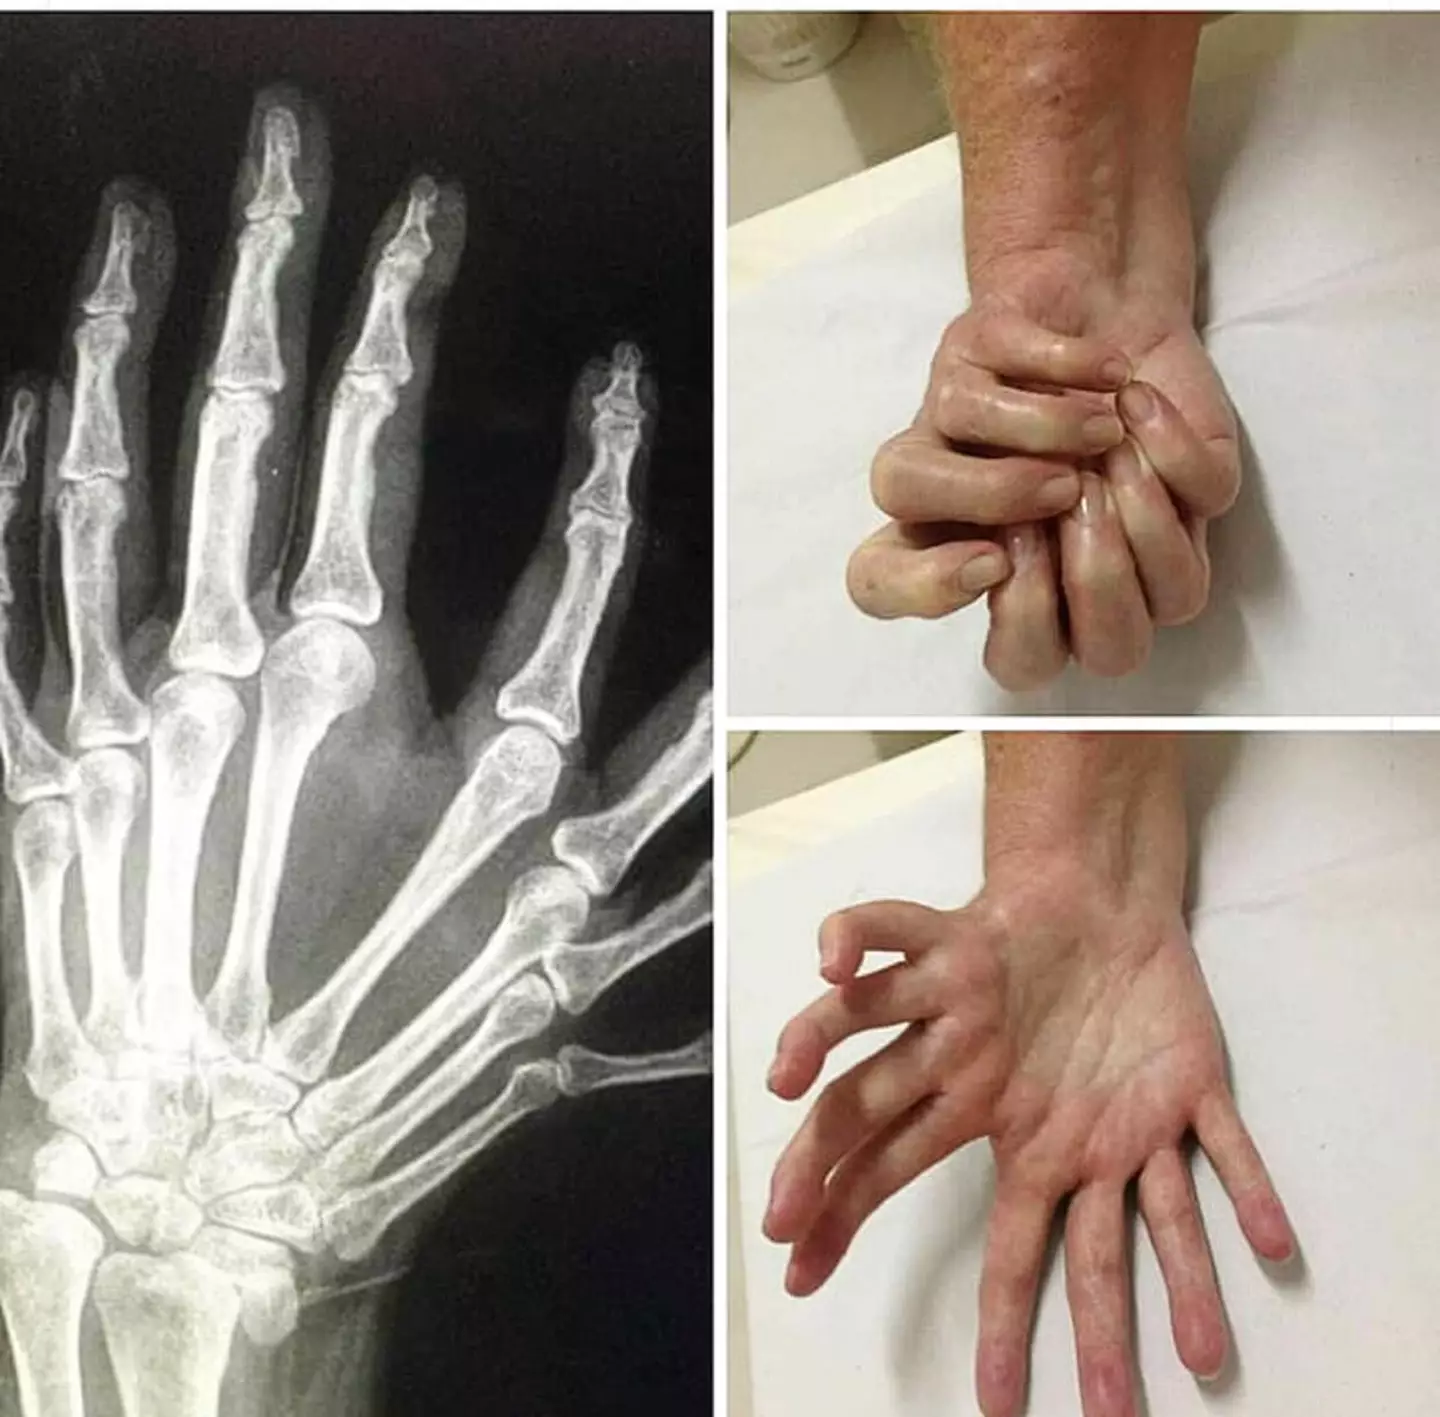

Mirror hand is an incredibly rare congenital condition, and for the most part it leaves people with mirror symmetry on their hand with a digit in the middle and usually three digits on the side, but no thumb.

When it is seen, the person usually has seven or eight digits, with the middle, ring and smaller fingers on either side of that central finger.

It can also cause limited movement in the fingers, forearm, and hand, as well as causing differences in the forearm and elbow.

In one case documented by the US National Library of Medicine, a two-month-old girl was brought to the doctor for the reason of polydactyly - extra digits - and had some of the fingers amputated.

As you can see from the pictures, she had several surgeries which resulted in her having the ordinary number of fingers on her hand.